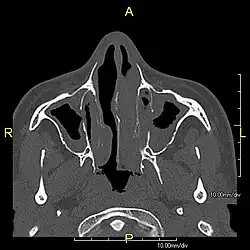

When accompanied by the combination of situs inversus (reversal of the internal organs), chronic sinusitis, and bronchiectasis, it is known as Kartagener syndrome[3] (only 50% of primary ciliary dyskinesia cases include situs inversus).[11]